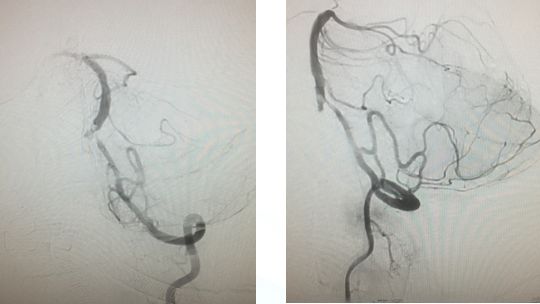

造影右侧椎动脉闭塞,右侧颈总动脉

左侧颈总、左侧椎动脉

左锥造影V4段先天性病变(狭窄?)

右椎入路微导管手推造影,寻找血管闭塞位置

右椎V4段狭窄,2.5*15球囊扩张(应用替罗非班)

13:40:应用3.0*13Apollo支架释放血管再通